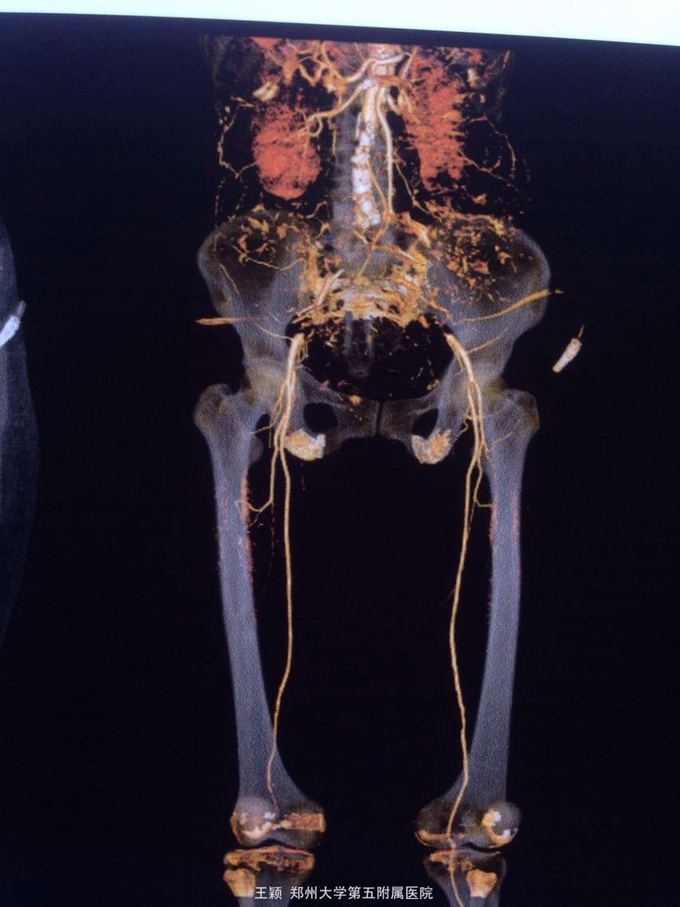

突发双性下肢疼痛,麻木,发凉半天。既往房颤病史,未规律抗凝治疗,突然发病,急诊入院。

双下肢皮色紫绀,皮温凉,末梢循环差,右侧显著,双下肢各动脉搏动均未触及未见溃疡及张力性水疱。彩超示左房内可疑血栓形成,心律不齐

腹主动脉骑跨栓,心律不齐 房颤 急诊全麻下行双股动脉切开去栓及造影术,术后抗凝,解痉,改善循环,营养神经,抗炎,利尿及碱化尿液,监测肾功能,电解质等,随时准备透析治疗